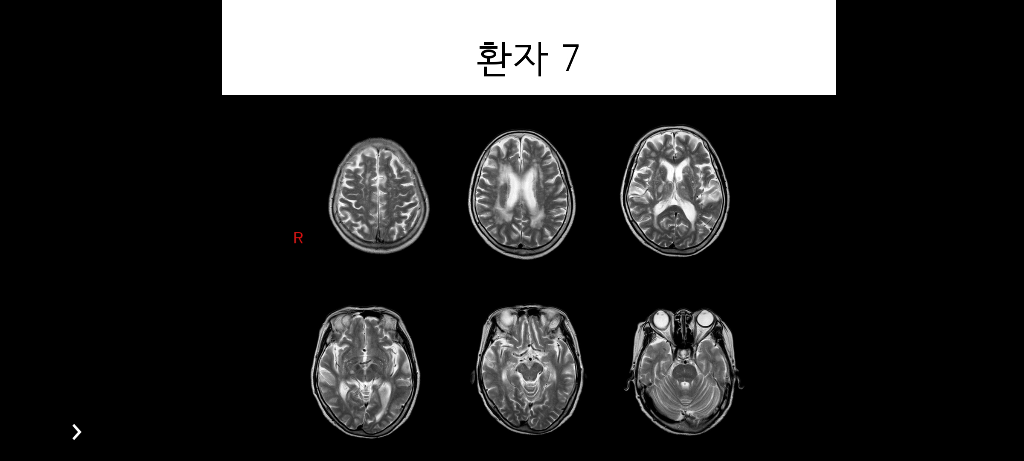

환자 뇌 mri 샘플 영상입니다 환자가 어떤 질환을 가진것인지 판단 근거는 어떻게 되는지 알고싶어서 질문 남깁니다. 왼쪽 뇌가 커진건지 오른쪽 뇌가 작아진건지도 궁금합니다

왼쪽 뇌가 커지지도 오른쪽 뇌가 작아지지도 않았습니다. 전반적인 뇌위축이 있으며 SVD소견이 보입니다. 그 외 양쪽 thalami에 high SI가 보이는데 올려주신 사진이 너무 작고 T2사진만 올려주셔서 판단에 제한이 있습니다. 다른 시퀀스 사진이나 임상정보가 있으면 도움이 되겠습니다.